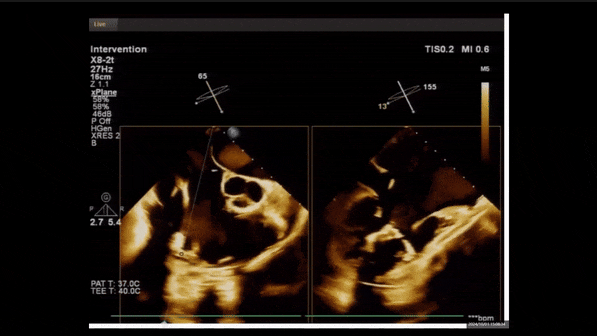

術(shù)前TEE評估

1、3D TEE顯示雙房及右室擴(kuò)大,右室中段直徑40mm,右室FCA 52%。三尖瓣環(huán)TAPSE 22mm,三尖瓣環(huán)左右徑49mm,三尖瓣隔葉長度16mm,前葉長度21mm,后葉長度34mm,三尖瓣前隔gap 11mm,后隔gap 5.6mm,AP gap 12mm,診斷極重度功能性三尖瓣返流(Type I型三尖瓣:Torrential FTR 5+)。

2、彩色多普勒顯示:收縮期三尖瓣口返流束起源于后隔交界、前后葉之間及前隔交界,返流束縮流頸最大寬度27mm,三尖瓣返流口EOA=2.02cm2,返流容積124ml,收縮期三尖瓣返流峰值速度2.64m/s,返流峰值壓差28mmHg,PAPs 43mmHg,舒張期三尖瓣口平均跨瓣壓差1mmHg,肝左靜脈可見明顯逆向血流波。

術(shù)中經(jīng)食道超聲輔助下可見LuX-Valve Plus夾持件抓捕瓣葉狀態(tài)良好,夾持件在位,室間隔錨定位置良好,假體瓣膜整體錨定狀態(tài)穩(wěn)固。